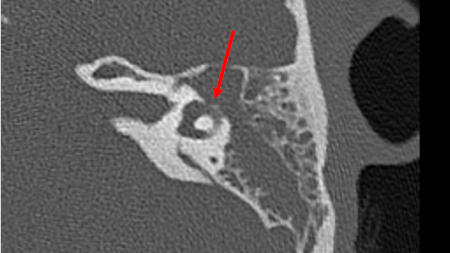

Labirintite e neurite vestibular

TC axial (sem contraste) do osso temporal da orelha esquerda demonstrando erosão direta no canal semicircular horizontal pelo colesteatoma

Da coleção pessoal da Dra. Tiffany Hwa; usado com permissão